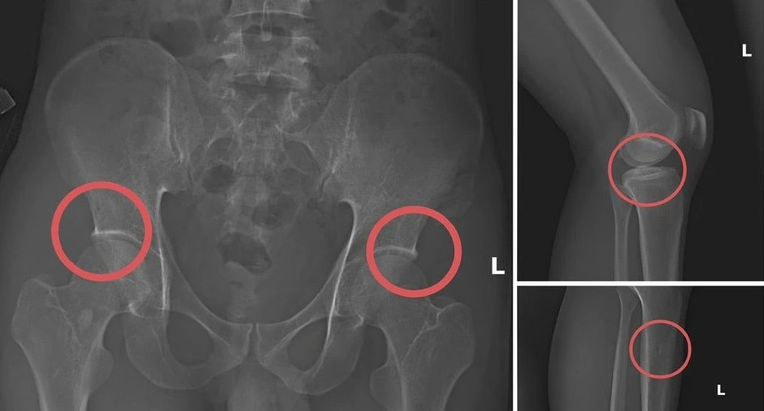

Bản phim chụp XQ một số tổn thương xương do đối tượng tạo ra nhằm trục lợi tiền bảo hiểm nhân thọ.

Trong giai đoạn “gây thương tích”, Châu bị cáo buộc trực tiếp tiêm thuốc mê cho người tham gia, sau đó sử dụng kim, búa, đinh để tác động lên xương, tạo ra vết nứt hoặc vỡ, giống như tai nạn thực sự. Khi thương tích đã “xong”, Châu hướng dẫn các đối tượng dựng hiện trường giả (như điện giật, ngã suối) để giải thích thương tích trong hồ sơ y tế và yêu cầu đền bù.

Lãnh đạo Công an tỉnh Phú Thọ đánh giá rằng thủ đoạn này rất “tàn nhẫn, vô nhân tính”: Châu không chỉ coi thường sức khoẻ, tính mạng người tham gia, mà còn rất tính toán, chọn vị trí gãy xương để tối đa hóa quyền lợi bảo hiểm, khiến công ty bảo hiểm khó phát hiện gian dối.